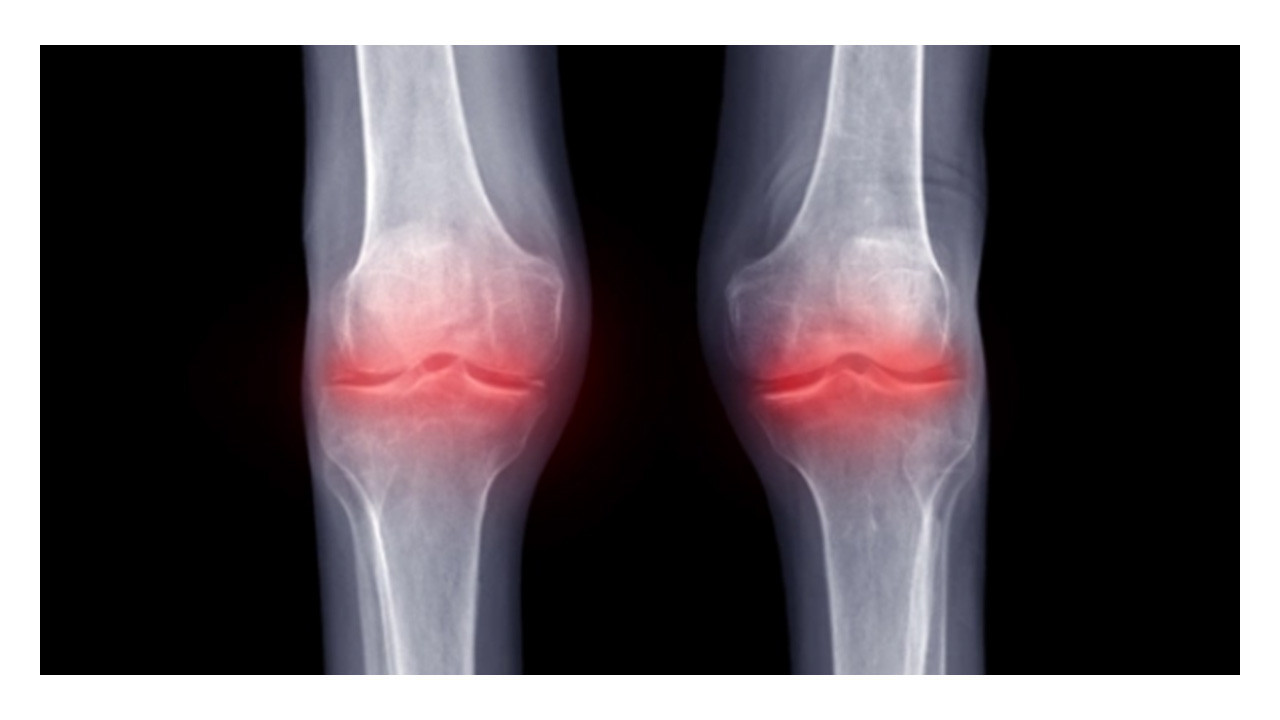

Sık karşılaşılan sağlık sorunlarından birisi olan eklem kireçlenmesinin (osteoartrit), eklem kıkırdağının zamanla aşınması ve bozulmasıyla ortaya çıkan ağrı, hareket kısıtlılığı ve yaşam kalitesinde düşüşe yol açan yaygın bir rahatsızlık olduğunu belirten Doç. Dr. Koca, kireçlenmenin en sık diz, kalça ve el eklemlerinde görüldüğü ifade etti. Dr. Koca, eklemlerin kireçlenmesine karşı geleneksel tedavi yöntemleri arasında ağrı kesici ilaçlar, fizik tedavi uygulamaları, eklem içi enjeksiyon tedavileri ve ileri durumlarda cerrahi müdahaleler önerilmekle birlikte son yıllarda rejeneratif (onarıcı) tıp alanındaki gelişmelerin hastalar için ameliyatsız yeni tedavi seçenekleri sunduğunu söyledi.

Diz kireçlenmesinde ve menisküs hasarında eksozom tedavisinin amacının eklem kıkırdağının ve menisküslerin yenilenmesini desteklemek, iltihabı azaltmak ve hastanın ağrı ile hareket kısıtlılığını hafifletmek olduğunu belirten Dr. Koca, "Eksozomlar, steril koşullarda diz eklemine enjekte edilerek uygulanır. Bu sayede; inflamasyonu azaltıcı etkiler gösterir. Kıkırdak ve hasarlı bağ dokunun kendini onarmasını teşvik eder. Eklem sıvısının kalitesini artırarak eklem hareketlerini kolaylaştırır. Ağrıyı azaltarak yaşam kalitesini yükseltir" ifadelerini kullandı.